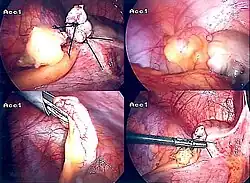

Laparoscopic appendectomy.

Laparoscopic view of a phlegmonous cecal appendix with fibrinous plaques, located in the right iliac fossa.

Laparoscopic appendectomy

Laparoscopic appendectomy was introduced in 1983 and has become an increasingly prevalent intervention for acute appendicitis.[95] This surgical procedure consists of making three to four incisions in the abdomen, each 0.25 to 0.5 inches (6.4 to 12.7 mm) long. This type of appendectomy is made by inserting a special surgical tool called a laparoscope into one of the incisions. The laparoscope is connected to a monitor outside the person's body, and it is designed to help the surgeon inspect the infected area in the abdomen. The other two incisions are made for the specific removal of the appendix by using surgical instruments. Laparoscopic surgery requires general anesthesia, and it can last up to two hours. Laparoscopic appendectomy has several advantages over open appendectomy, including a shorter post-operative recovery, less post-operative pain, and a lower superficial surgical site infection rate. However, the occurrence of an intra-abdominal abscess is almost three times more prevalent in laparoscopic appendectomy than open appendectomy.[96]